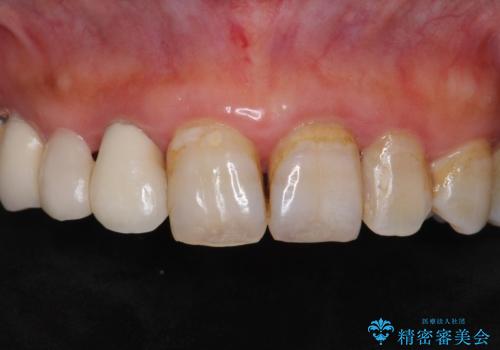

- 被せ物がかけてしまったことを主訴に来院された患者様です。

口腔内を精査したところ、右上のブリッジの内側(口蓋側)がかけており、下の前歯(右下1)には唇舌側に瘻孔を伴う大きな根尖病変ができていました。

ブリッジとクラウンの自然な仕上がりと咬み心地に喜んで下さいました。

精密な根管治療により、下の前歯の歯ぐきにできていた瘻孔もなくなりました。